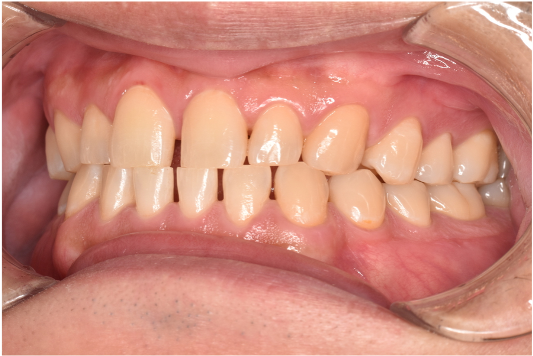

general 30代男性「タバコのヤニが気になる」縁上歯石・着色を除去し、その後歯周治療を行った症例

治療後

| 行ったご提案・治療内容 | 初診時はブラッシング方法などセルフケアについて説明を行い、縁上歯石・着色の除去を行いましました。 歯肉の炎症がある程度落ち着いたところで、後日再評価を行い歯周治療へ移行しました。 |

| 術後の経過・現在の様子 | 綺麗になったと喜んでいただき、この状態を保てるようセルフケアにも力を入れてくださっています。3ヶ月に一度の定期検診にも通っていただいています。 |